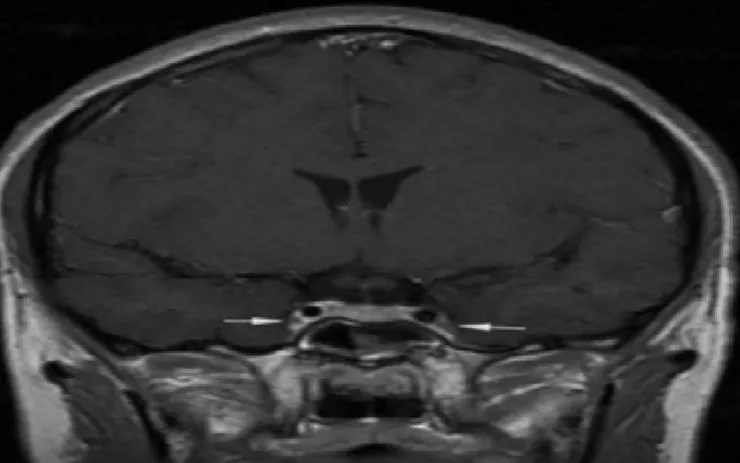

Kết quả chụp cộng hưởng từ sọ não cho thấy phù nề lan tỏa – dấu hiệu điển hình của viêm tắc tĩnh mạch xoang hang, một tình trạng huyết khối nhiễm trùng ở nền sọ. Dù được điều trị tích cực bằng kháng sinh mạnh và thuốc giảm phù não, tiên lượng bệnh nhân vẫn rất nặng do tổn thương lan vào não, màng não và mạch cảnh trong.